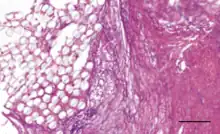

The Ligament Advanced Reinforcement (LARS) is a leading artificial ligament in ACL repair surgery. They are made of polyethylene terephthalate (PET).[3] They consist of an intraosseous and an intra-articular portion. The intraosseous section consists of longitudinal fibers bounded by a knitted transverse structure. This knitted structure can help prevent deformation and abrasion.[5][11] The intra-articular portion is made of longitudinal fibers pretwisted at a 90 degree angle. This section is designed to resist fatigue and promote tissue ingrowth.[5] Leeds Keio ligaments consist of a polyester mesh structure. It seeks to mimic the mechanical properties of the native ACL. The porous nature of the ligament can promote tissue ingrowth which has been shown to improve mechanical properties.[5] The PGA Dacron artificial graft consists of 75% braided biodegradable polyglycolic acid and 25% permanent Dacron thread.[11] The Kennedy LAD artificial ligament is made of polypropylene ribbons. It is designed to promote tissue ingrowth and the progressive transfer of load onto the new ligament.[10]

Coatings have been added to artificial ligaments to improve their biocompatibility. 58S bioglass and hydroxyapatite coatings have been shown to improve osseointegration and cellular activity in vitro and in animal studies[3] when deposited onto PET ligaments using the soaking method.[2][3] Hydroxypropyl cellulose surface treatments have been shown to improve osseointegration for PET ligaments in animal studies.[2] Uncoated PET is hydrophobic, so coatings are designed to improve hydrophilicity.[3] Hyaluronic acid coatings can reduce hydrophobicity and have been shown to reduce scar tissue formation and inflammation in vivo.[3] Hyaluronic acid and chitosan composite coatings can be deposited onto artificial ligament surfaces by the layer-by-layer technique, and they have been shown to enhance new bone formation at the ligament interface in mice.[9] The chitosan is used to reduce hydrophobicity and improve osseointegration and mineral deposition, while the hyaluronic acid promotes cell differentiation and growth.[9] Poly(sodium styrene sulfonate) coatings have been shown in animal studies to improve knee functionality and mimicry of the native ACL.[2][13]